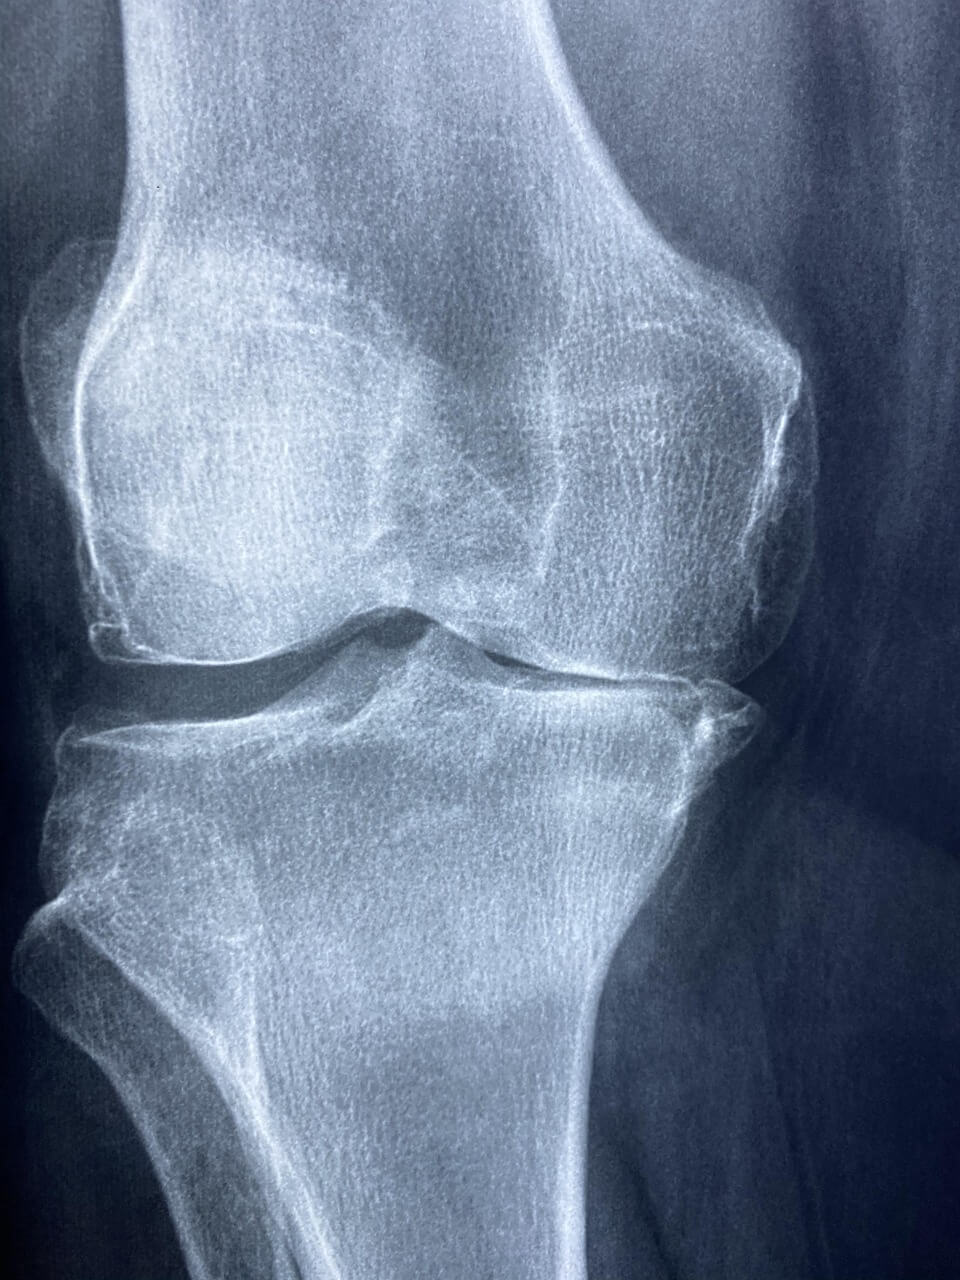

중년 이후 손가락이나 무릎, 어깨 통증을 느끼는 분들이 많습니다.

주로 손가락, 무릎, 어깨, 허리 부위가 쑤시거나 뻣뻣해지는 형태로 나타납니다.

류마티스 관절염이란 무엇인가요?

류마티스 관절염은 자가면역 반응으로 인해 관절에 만성 염증이 생기는 질환입니다. 단순한 노화 통증과 달리 면역 이상이 원인이기 때문에 조기 진단과 치료가 중요합니다.

특히 아침에 1시간 이상 손가락이 뻣뻣하거나, 양쪽 관절이 대칭으로 붓는 경우는 단순 갱년기 통증과 구분이 필요합니다.